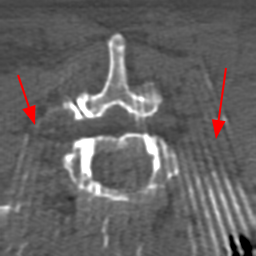

Disentanglement and explicit shape constraints. As shown in Fig. 4, we can see streak metal artifacts nearly everywhere in . M1 can roughly disentangle artifacts and anatomical information but strong vertical artifacts and strange air area appear in (see red arrows of M1 in Fig. 4). For the anatomical structure, M1 learns to segment vertebrae with fully supervised and applied on various CT images, but fails to suppress the false bony structure in and as may misclassify some metal artifacts as bone.

Implicit shape constraints. With , all segmentations are improved with higher Dices and smaller ASDs, see Table 1. As shown in Fig. 4, , and become similar but the high density bone is not correctly segmented in as it maybe treated as metal artifacts. Comparing between M2 and M1, the abnormal air region disappears but metal artifact reduction performance is still not satisfactory.

Anatomy-aware generation. With AADE layer in M3, , and are substantially improved as shown in Table 1. Note, is used as attention map, so we do not expect it to be identical to . In , metal artifacts are further suppressed comparing with M2. Thus, AADE is critical to our anatomy-aware artifact disentanglement framework. With the special structure, can be punished in the image translation and reconstruction processes and the other encoders and generators receive more guidance. However, as shown by blue arrows in Fig. 4, we observe a shadow of vertebra edge of appears in of M3 and the vertebra boundaries get smoothed out in . It may be because sharp edges are encoded as metal artifacts and forced to be added to by artifact consistency loss .

Removal of . To mitigate vertebrae shadows, we remove . The segmentation performance of most images in M4 gets improved because of better synthetic images. Overall, in M4 yields the best segmentation performance for CBCT images with an average Dice of 0.847 and an average ASD of 1.54 mm. For the synthetic images, M4 generates with the best quality and least metal artifacts among all the models. M4 also outputs without vertebra shadows. The results indicate our shape-aware network could preserve anatomical details and transfer the metal artifacts precisely without .